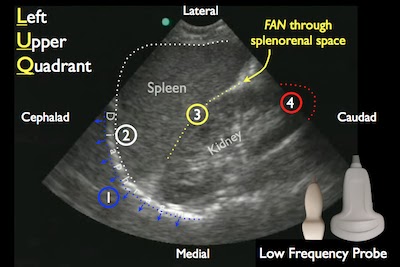

- Component: FAST abdominal views

- Probe: Phased array probe (3.5 – 5 MHz)

- Location: Hepatorenal recess, Splenorenal recess, and bladder

- Finding: Internal blood loss